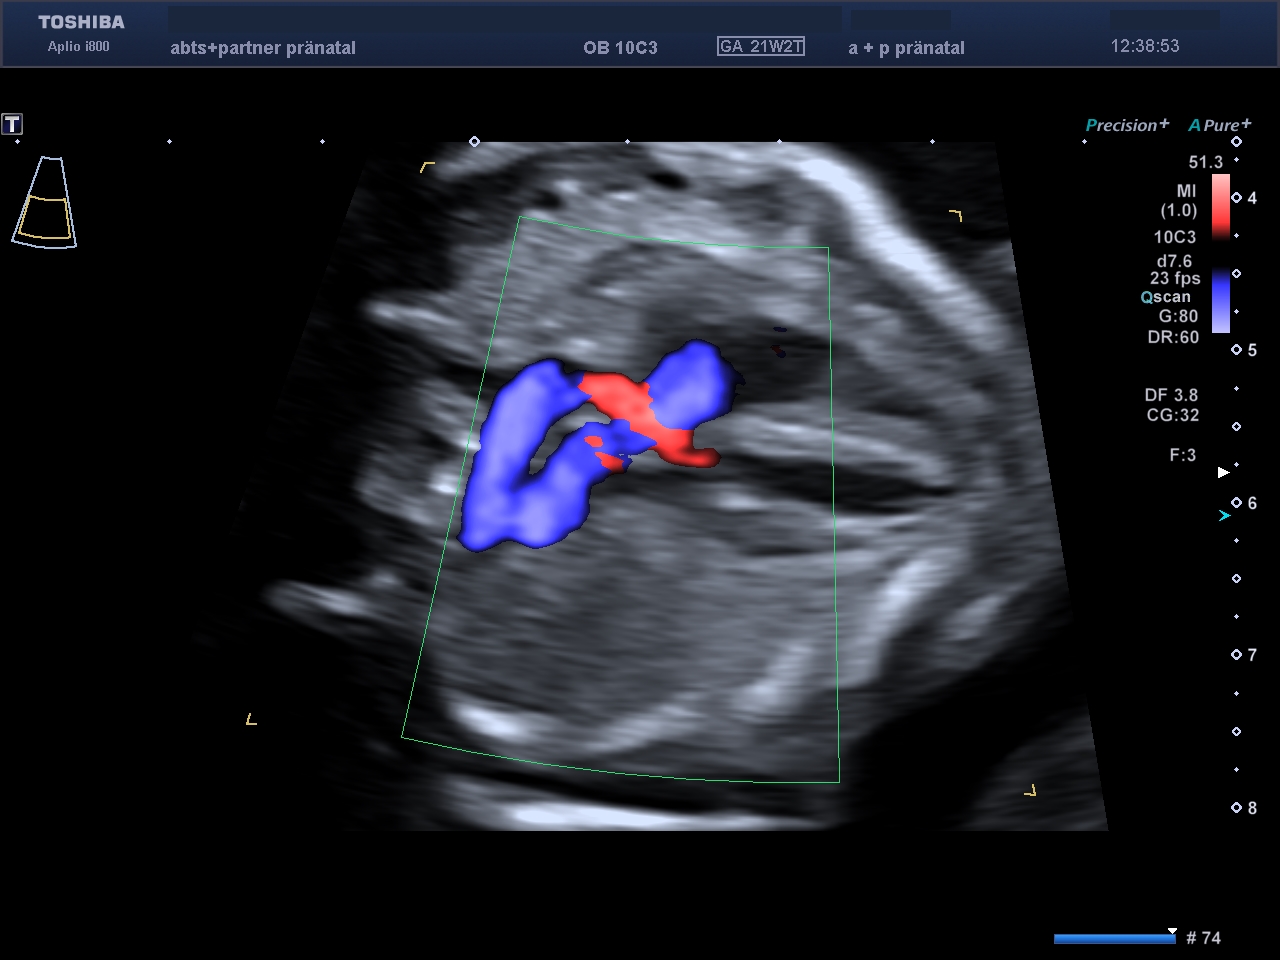

Das kindliche Herz zeigt normale Anatomie und unauffälliges Blutflussmuster.

Mit der Nabelschnur fließt der Sauerstoff vom Mutterkuchen direkt ins kindliche Herz. Das Blutflussmuster zeigt einen normalen Fluss, so ist die Wahrscheinlichkeit für Herzfehler und die Trisomie 21 gering.